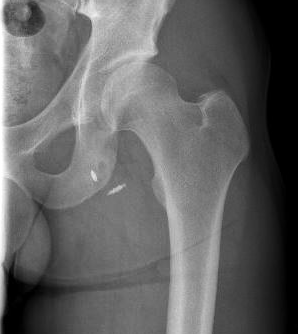

Xray

Exclude bony avulsion